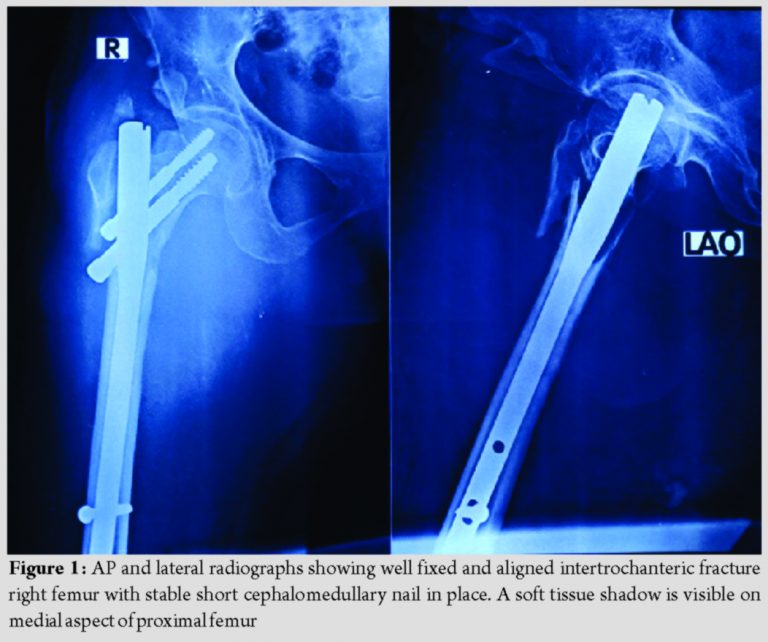

A 65-year-old lady had a domestic fall following which she was taken to a private hospital nearby where she was diagnosed as having intertrochanteric fracture of the right femur and was operated the next day with short cephalomedullary nailing. The operation was uneventful, and she was recovering well with subsequent rehabilitation post-surgery. She started noticing a slowly enlarging painful swelling in her medial aspect of the right thigh after a month of surgery. She was also complaining of weakness and vertigo and, therefore, was taken to the index surgeon. After reviewing fresh radiographs, which was reported unremarkable, the treating surgeon referred her to a general physician. Her hemoglobin was found to be on the lower side (6.9 g/dl) for which she had undergone two units of packed red cell transfusion and was advised iron supplement. She remained fine for a few weeks, but again, her condition started deteriorating and was kept on symptomatic management and received two more units of packed red cell transfusion. Finally, she was referred to our institution for further management 3 months after the index surgery. She was ambulatory with walker support. Past medical history included hypertension and rheumatoid arthritis. On examination, she looked pale and her vitals were stable. There was a tender, firm, ill-defined swelling over anteromedial aspect of the proximal part of right thigh; there was no erythema, overlying skin was intact, regional lymph nodes were not palpable, and hip range-of-motion of the affected side was painful. There was no pulsation or bruit felt over the swelling, and her distal pulses and capillary refilling were optimum. Routine laboratory, biochemical, and coagulation parameters were within normal range except for low hemoglobin levels (8.2 g/dl). Repeat radiographs of the extremity revealed satisfactory alignment and fixation of Intertrochanteric fracture with short cephalomedullary nail; there was a soft tissue shadow on medial aspect of the proximal femur with no evidence of calcification, cortical erosion, or periosteal reaction (Fig. 1).

Pseudoaneurysm represents a pulsating encapsulated hematoma resulting from partial arterial vessel damage which possesses a permanent arterial blood circulation through its communication with the adjacent vessel. Profunda femoris artery is the most common culprit in thigh because of anatomical virtue of its close relationship with the proximal femur. Injury can be perpetrated by various non-iatrogenic or iatrogenic factors such as spike of displaced lesser trochanter or other bone fragments, forceful traction, deep posteromedial placement of retractors, clamps, overshot drill bit, and tap protruding from the medial femoral cortex, and large protruding screws [4,5,6]. Barquet et al. in their systematic review pointed out iatrogenic factors being the prevalent mechanism (96.15%), and its association with A2 trochanteric fractures predominate [1]. Moreover, traction during fracture fixation elongates and fixes the vessels, and with added adduction and internal rotation, PFA came to lie in the proximity of proximal femur, making it susceptible to injuring agent [6,7]. For obvious reasons, elderly patients with atherosclerotic rigid and fragile arteries are more prone to develop PSA [1]. In our patient, the location of PSA appeared more proximal, away from the protruding distal locking screw tip which is in contrary to the usual location of PFA pseudoaneurysm opposite to the 3rd/4th screw hole of DHS side plate, which also corresponds to distal interlocking screw hole site of the short nail (Fig. 1 and 3) [4]. We surmise inadvertent placement of retractor proximally during fracture manipulation and reduction, or misplaced and overshot guidewire during placement of proximal lag screws could have caused partial vessel damage. Guidewire could easily go astray in osteoporotic bone in this elderly lady with rheumatoid arthritis. Intuitively, the onset of symptoms is more acute in the case of iatrogenic injury, whereas slow vascular erosion by impinging protruding screw leads to delayed presentation [7,8]. Our case assumes significance since it presented late despite the most probable mechanism of being iatrogenic in nature. Clinical presentation varies widely based on the nature of the injury and can present acutely or on delayed fashion weeks, months, or years later [2,7,8]. Chong et al. described a triad of thigh swelling, bleeding from the incision site, and anemia with the falling trend of hemoglobin as the warning signals [9]. Pulsatility and systolic bruit are hard to ascertain due to the deep location of PSA. Distal limb perfusion is seldom compromised unless it is associated with occlusive disease of the superficial femoral artery [2,9]. Clinical features are subtle and nonspecific which are most often attributed to usual post-operative thigh swelling, moderate anemia, and weakness and can mask the diagnosis [1]. Moreover, diagnostic dilemma arises since PSA can mimic local soft-tissue hematoma, inguinal lymphadenopathy, abscess, DVT, or even soft tissue sarcoma. Timely diagnosis is paramount to avoid sinister complications such as rupture with massive hemorrhage, infection, compartment syndrome, mass effect on the adjacent structure causing tissue destruction, neuropathy, venous obstruction, and thromboembolism [2,3]. Diagnostic delay also prevailed in our case due to non-specific, innocuous clinical features; post-operative thigh swelling with unremitting anemia could have aroused suspicion earlier had there been proper scrutiny by the index surgeon. Therefore, the merit of this case lies in keeping surgeons abreast about this entity. Clinical suspicion can be aided by appropriate diagnostic modality. Plain radiographs usually are unremarkable, albeit can show cortical scalloping of the proximal femur in long-standing cases [7]. Duplex ultrasound is the initial modality of choice which can delineate size, extent of the sac, and presence of thrombus. CT angiography, a superior non-invasive modality, allows better visualization and can aid in decision making. Digital subtraction angiography (DSA) is considered the gold standard for both diagnosis and therapeutic intervention. It can accurately delineate site, size, the feeding vessel of PSA, and the patency of distal flow [2,5,10]. Still, there is no consensus as to the gold standard treatment for PSA of PFA. Small (<1 inch) and asymptomatic lesions can be treated conservatively with the premise of spontaneous obliteration. For larger, symptomatic lesion a slew of treatment modalities are described ranging from surgical exploration (aneurysmectomy, repair, and ligation) to various sophisticated radiological interventions such as ultrasound-guided compression, percutaneous thrombin injection, endovascular treatment with embolization, or stent-graft placement [1,2,11]. Presently, endovascular interventions are emerging as the therapeutic modality of choice with surgery reserved for cases not amenable for endovascular treatment. Our patient was successfully treated with selective embolization (Fig. 3); it is increasingly being regarded as a safe, effective, and standard of care with the added advantage of avoidance of another surgical intervention in elderly, frail patients [3,8,11]. Orthopedic surgeons should be mindful about this uncommon yet ominous complication; diligent care ought to be taken for prevention. Excessive traction with adduction and internal rotation to be avoided during fracture fixation, limb should be brought to the neutral rotation with less traction during placement of distal locking screw of short intramedullary nails. Careful fracture manipulation, monitoring the displacement of lesser trochanter fragment, use of guarded drill bit and careful drilling, keeping retractor and clamp close to the bone to avoid deep posteromedial placement, and choosing appropriate size screw are some of the key factors to adhere to during surgery [1,4,6,7]. Extra care should be exercised during drill bit or guidewire introduction in osteoporotic bone. An astute surgeon should always keep a high index of suspicion and render appropriate diagnostic modality in case of any inexplicable post-operative thigh swelling to institute timely intervention.